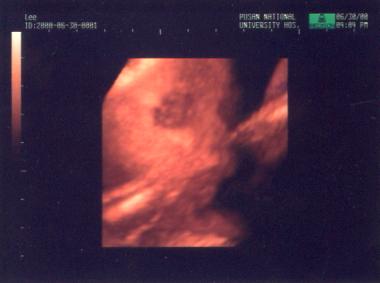

이제 태아 초음파 검사가 시작됩니다. 한 눈에 깜빡이가 엄청 자란 것을 볼 수 있었습니다. 오늘은 더 확실하고 자세하게 아기의 모습을 볼 수 있었습니다.  아기의 재태 일수를 계산해 보니  재태일수에 맞게 자라고 있었습니다. 초음파를 맞아서 그런지...아기는 계속 나부대고 있었습니다. 손을 흔들고 머리를 흔들고...마침  3D(3차원) 초음파라서 아기 얼굴을 3차원 영상으로 보려고 시도했는데 깜빡이가 어찌나 머리를 흔들어 대던지....3D 스캔하는 3-4초를 참지 못해 제대로 얼굴을 볼 수 없었습니다. 물론 25주에 무슨 얼굴이 나오겠느냐마는 ....

그래도 아쉽지만 옆모습은 조금 볼 수 있었습니다.

사진은 깜빡이의 옆 모습입니다. 선화는 이 사진을 보고 계속 아빠 닮아서 코가 큰 것 같다고 한 마디 합니다. 그래서 전 정말 아빠를 닮았나 자세히 봅니다....선화는 코와 눈 밑이 아빠를 닮았다는데.....전 잘 모르겠습니다.